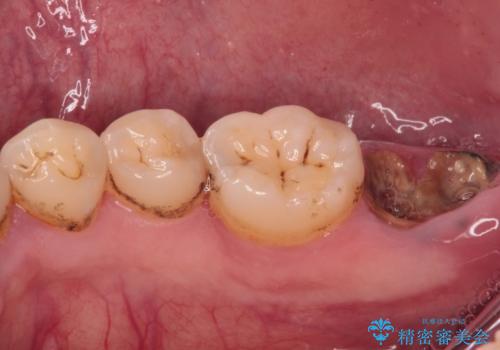

- 左下欠損部のインプラント治療を希望して来院された患者様です。

左下の欠損部を長期間欠損を放置していたことで、咬み合う上の奥歯が動いてしまっていたので、まずは上顎奥歯の部分矯正を行うこととしました。

理想的な咬み合わせに改善した上で、インプラント補綴治療を行うこととしました。

部分矯正を行ったこと治療期間は長くなりましたが、違和感のない咬み合わせを達成することができました。